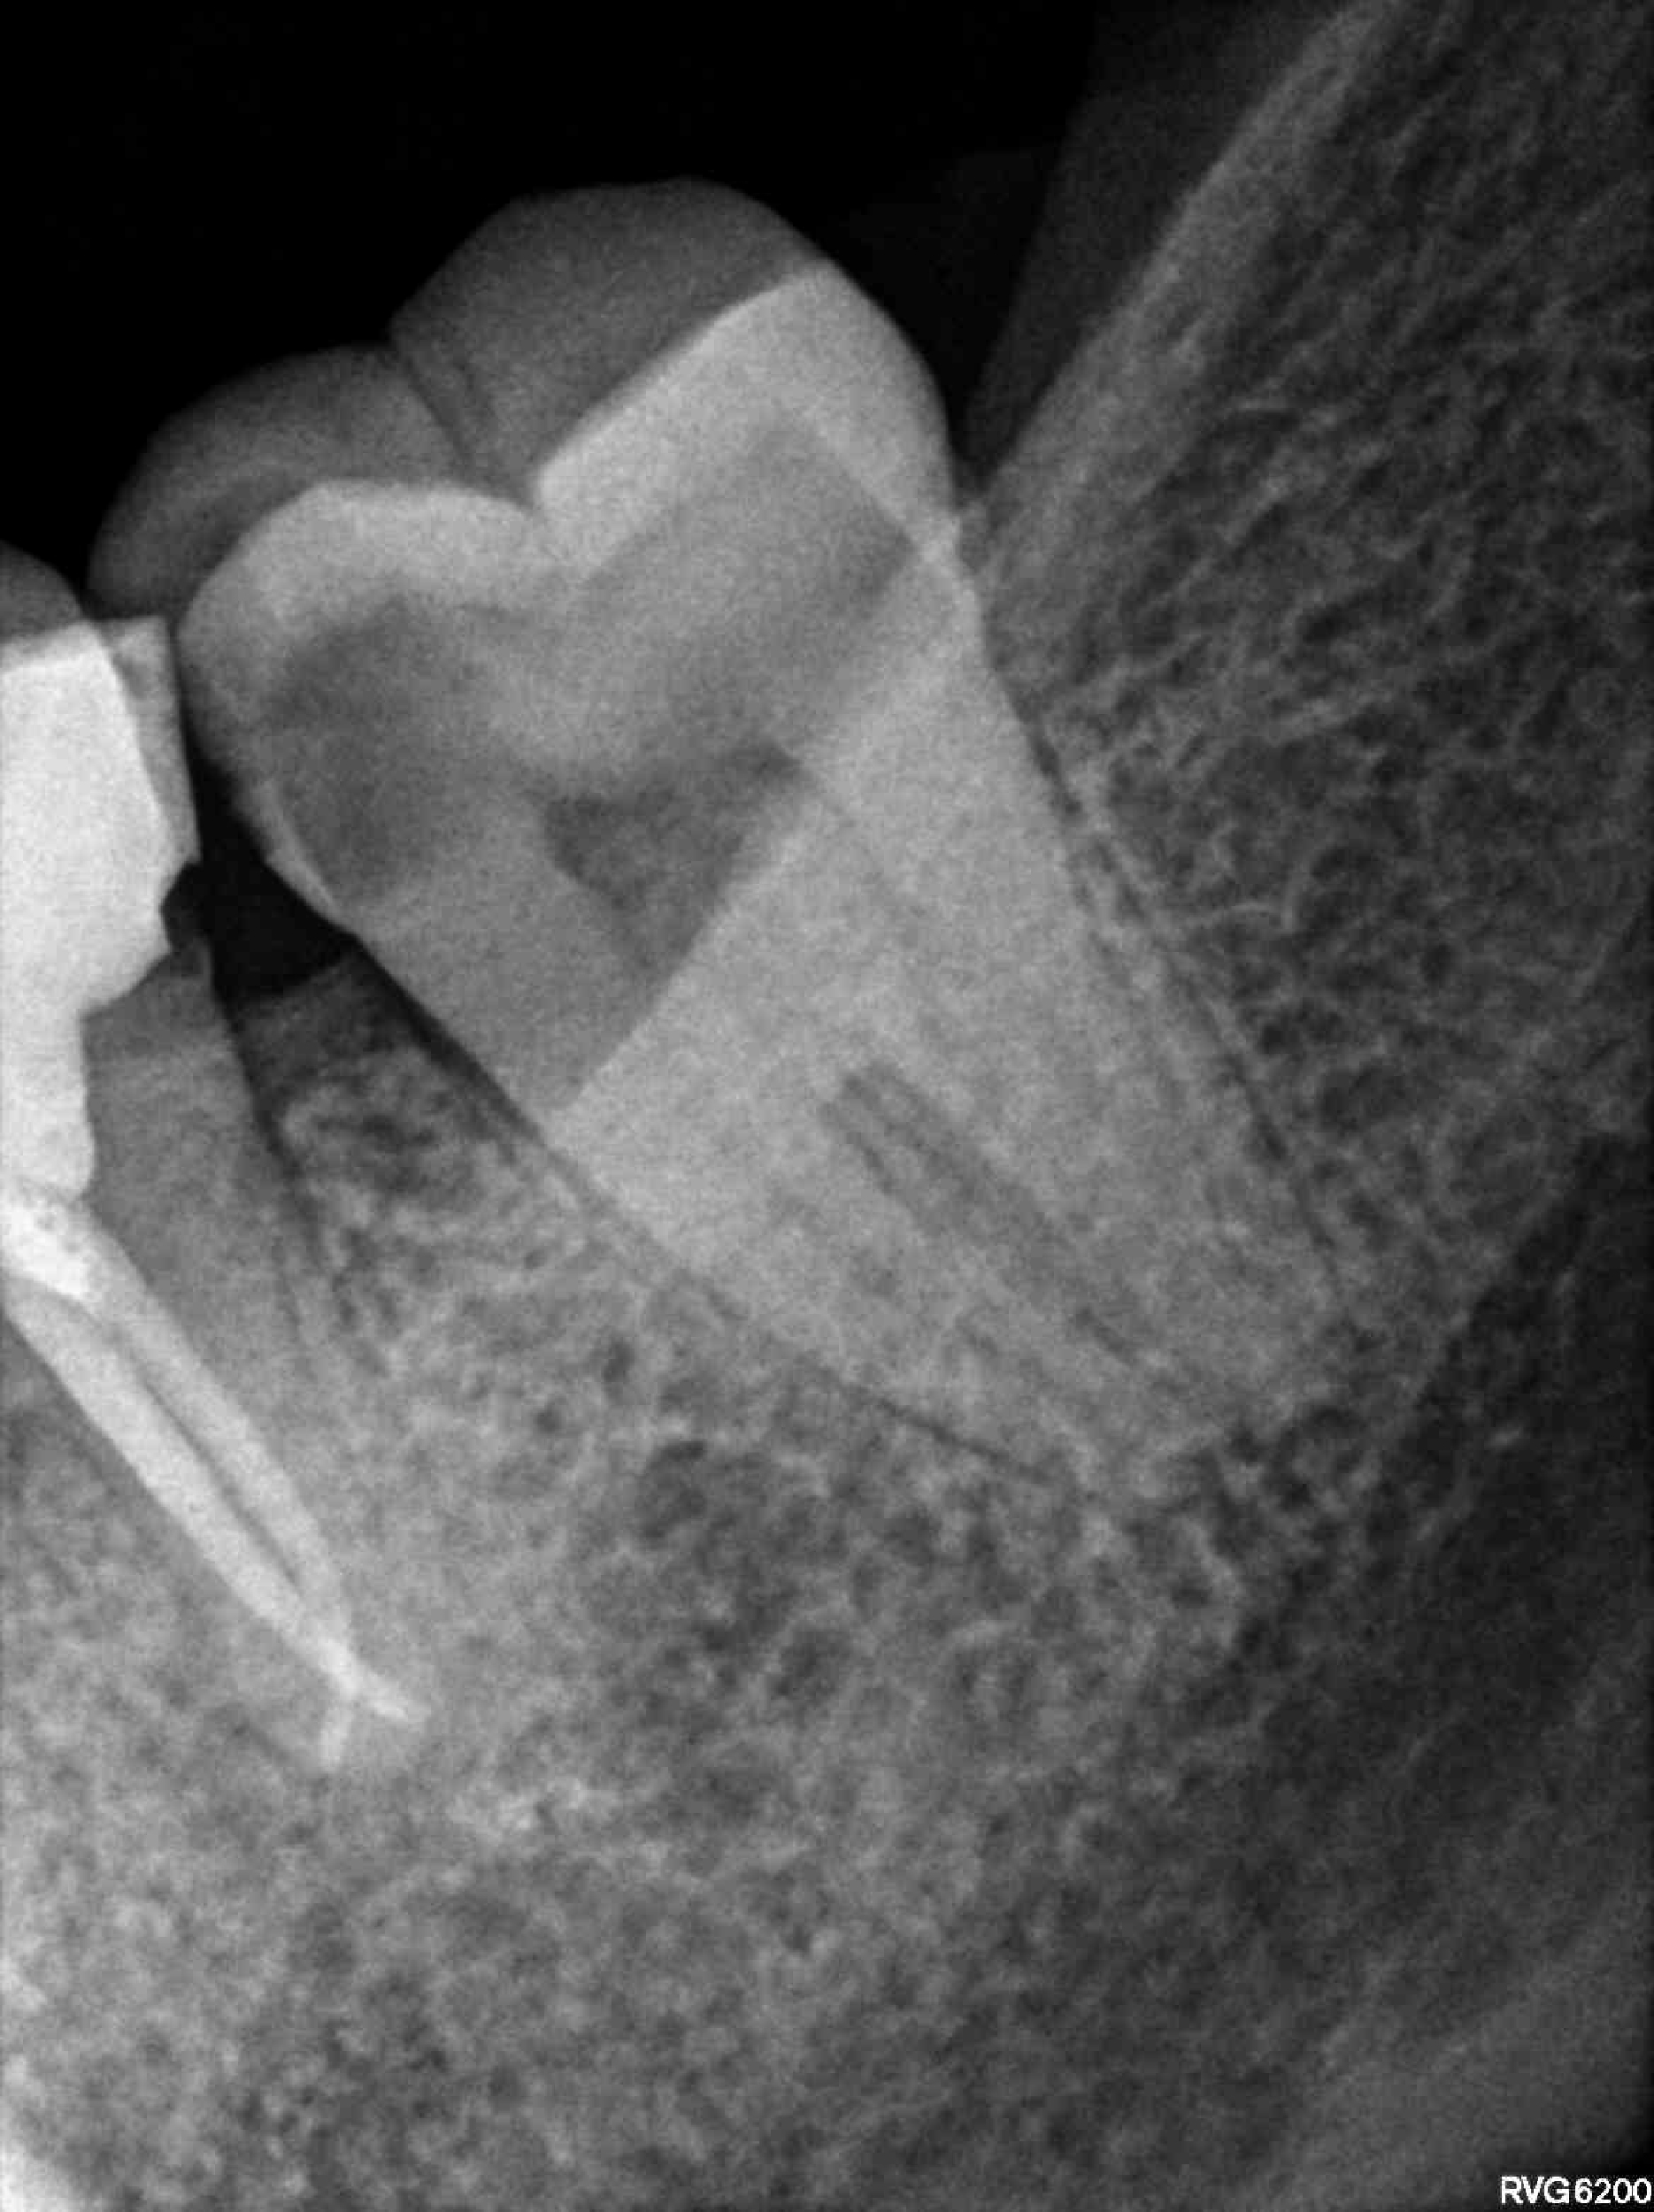

Categoría Endodoncia

Radiografías

Imágenes del tratamiento